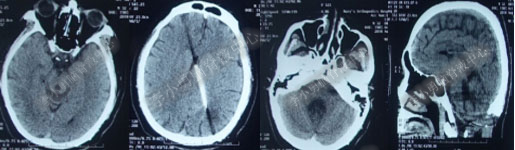

2017年6月19日(第1次内镜术后404天即一年零39天),因原症状加重,第2次住入该院。2017年6月20日(住院第2天),复查头部MRI(图-5)。

图-5:2017年6月20日头部MRI

2017年6月27日(分流术后5天),复查头部CT(图-6)显示幕上脑室及第四脑室均有所缩小。

图-6:2017年6月27日头部CT

图-7:2017年7月30日头部CT

图-8:2017年9月18日头部CT

图-9:2017年10月15日头部CT